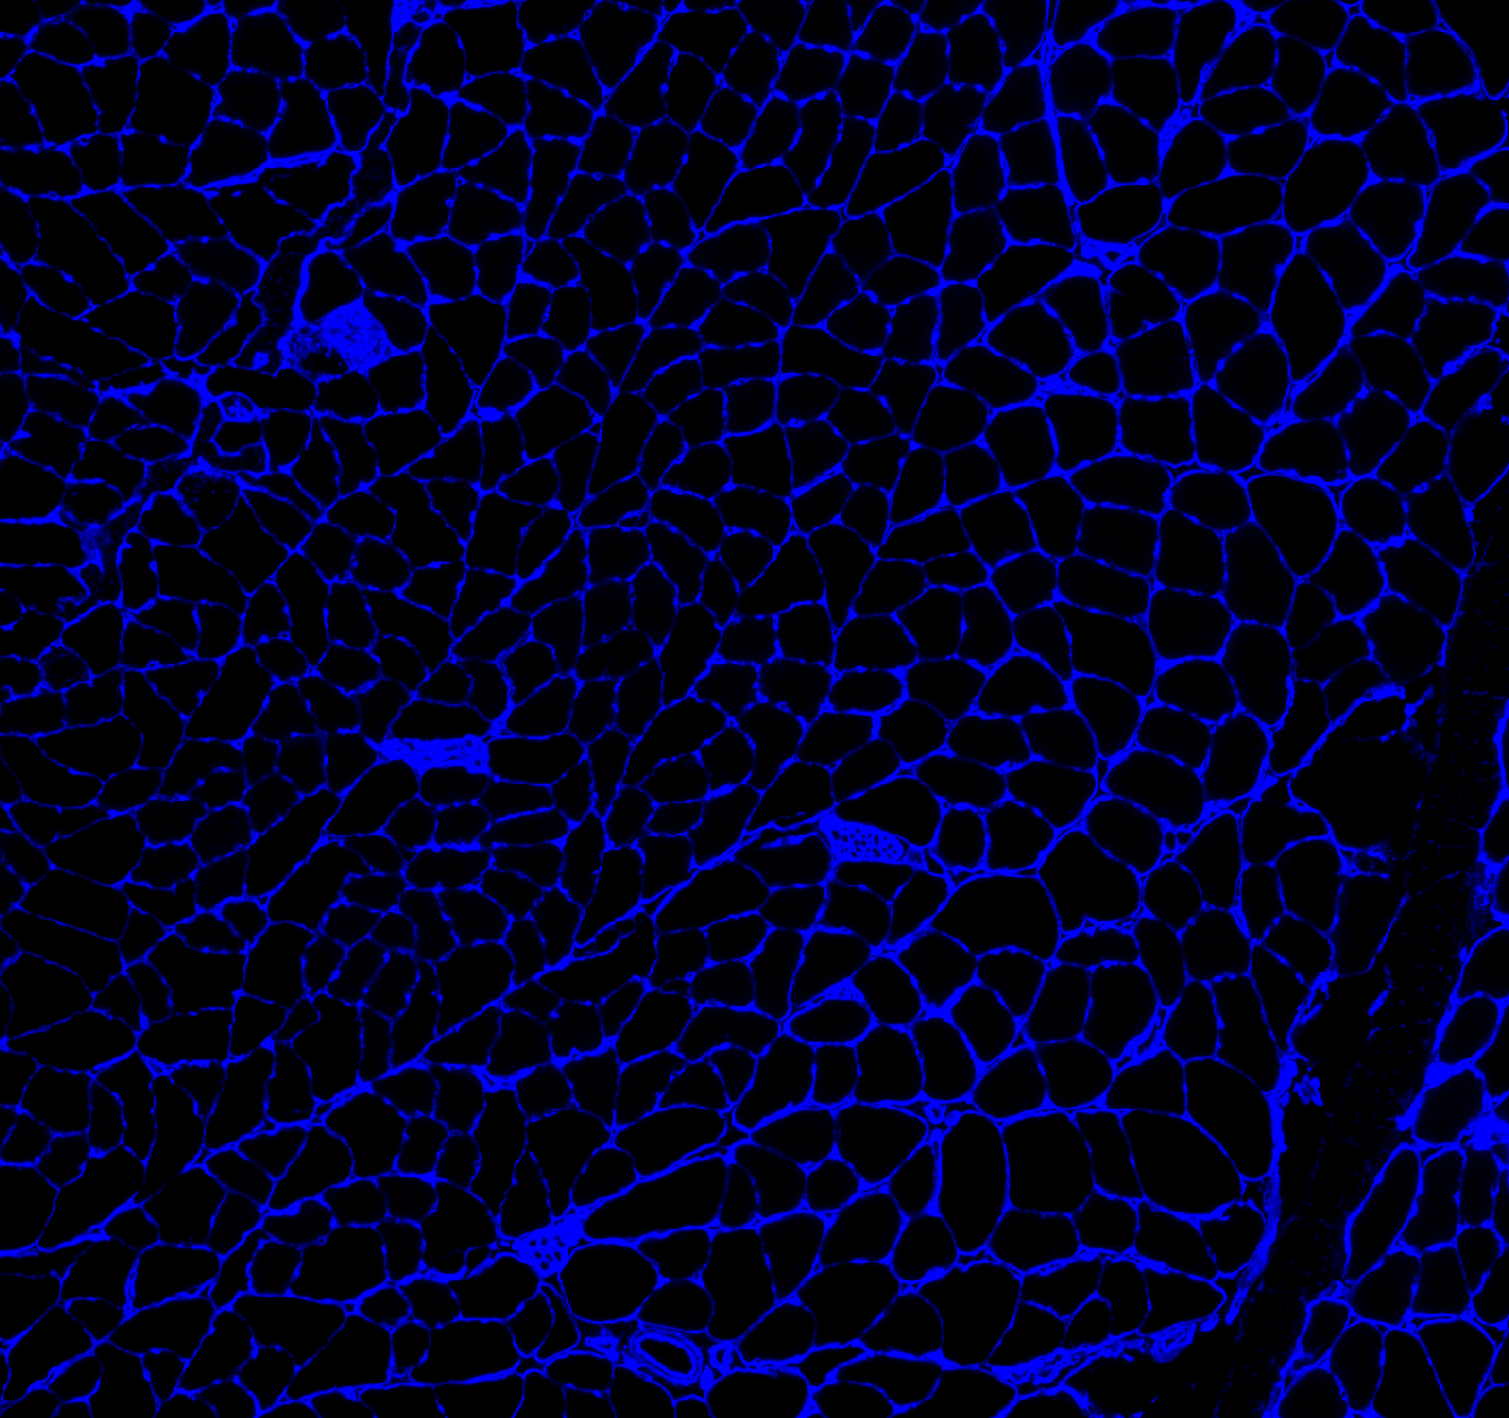

Here is the original image

-